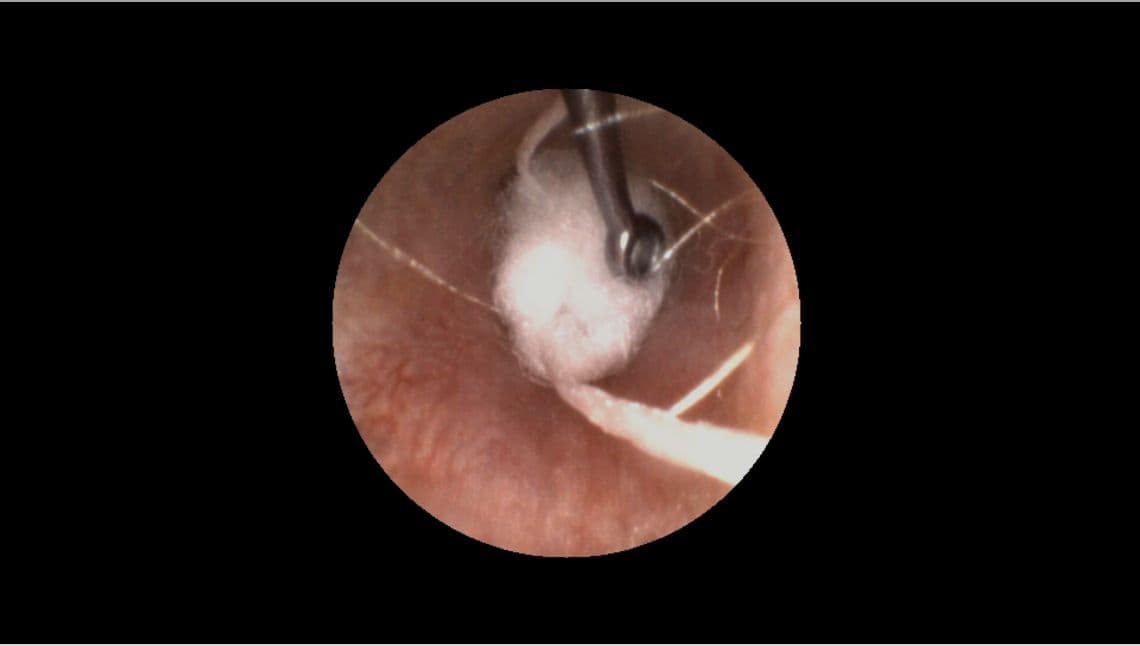

Step 2: Insert the otoblock

The size and type of otoblock you use makes a big difference in the outcome of your impression.

1. In most cases, we recommend using cotton, not foam, and flaring it before insertion.

2. Properly brace your hand against patient’s head.

3. Use your otoscope and a curette to guide the block past the second bend of the ear canal and place it as close as possible to the eardrum.

4. Once placed, check your work by inspecting the perimeter of the otoblock with your otoscope to ensure there are no gaps.

Pro Tip: Positioning yourself level to the ear, lifting up the pinna and pulling the tragus forward all help make it easier to see what you’re doing.